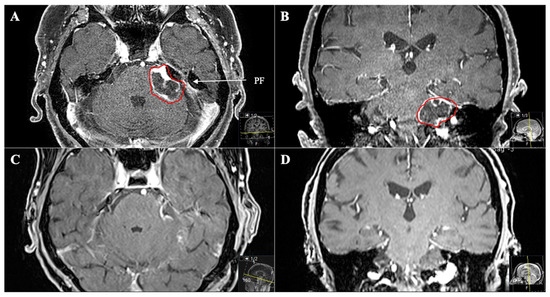

Figure 6. A 53-year-old female patient presented with vomiting, slight ataxia, facial pain and trigeminal hypesthesia (V1,V2) for three months. (A) Preoperative axial and (B) coronal T1-weighted gadolinium-enhanced MRI, showing a space-occupying cystic trigeminal schwannoma invading the cerebellopontine angle (Samii Type B). (C) Postoperative axial and (D) coronal MRI control, indicating complete resection via a retrosigmoid approach. Postoperatively, new temporary slight hypoacusis and facial neve palsy (House and Brackmann Grade III) occurred.